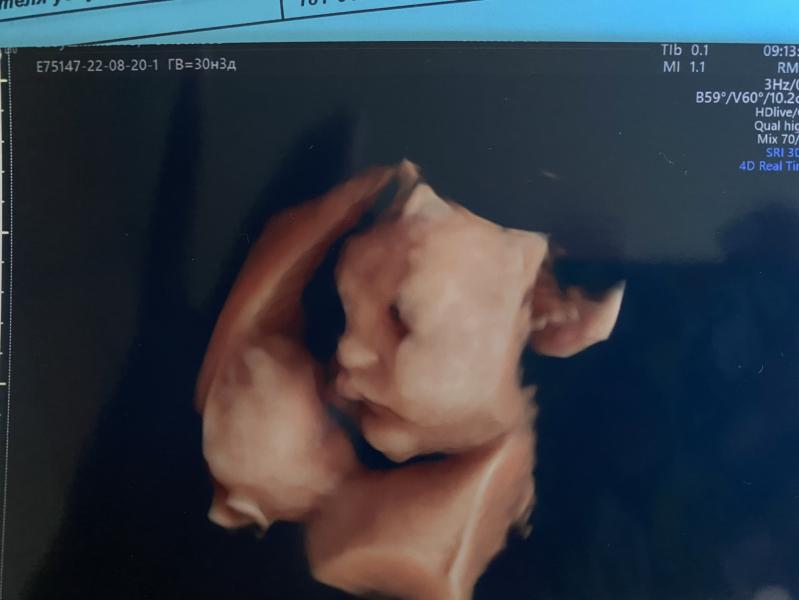

Ходили на последний скрининг на 30.3 недели

- многоводие ,но причину не нашли и сказали,что с малышом все Оки доки

- весим +- 2кг

- пуповины вокруг шеи нет

- все на месте у малыша и функционирует все у него хорошо.